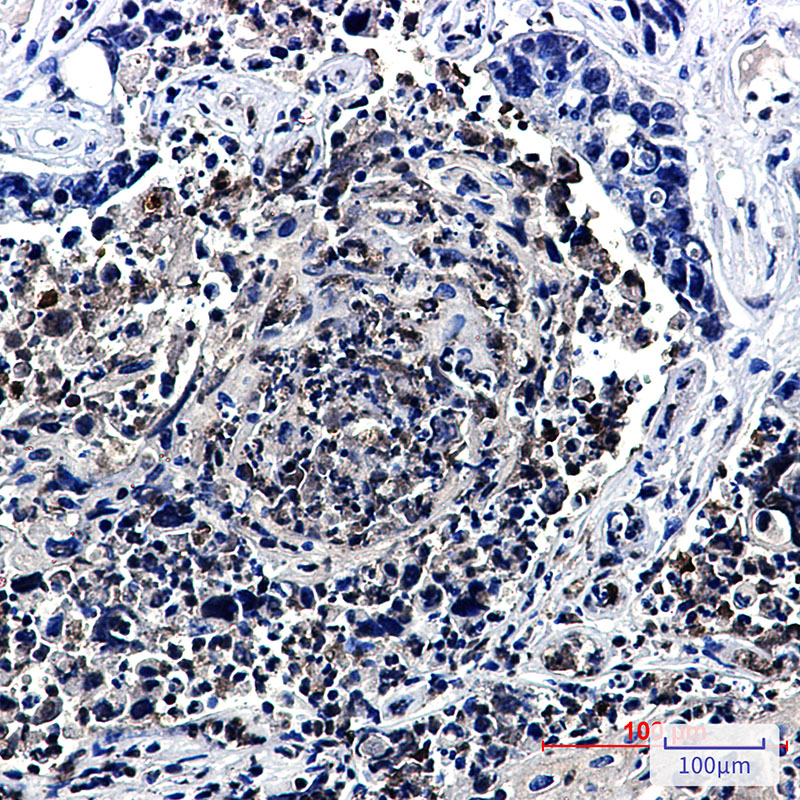

IHC 1/50-1/100 Human,Mouse,Rat

**摘要**: 通过免疫组化(HJURP抗体)发现HJURP在三阴性乳腺癌中高表达,且与患者不良预后相关,提示其作为潜在生物标志物的价值。